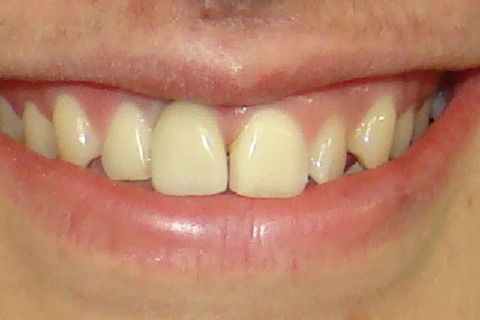

Foto frontal da paciente antes da reabertura

Sorriso da paciente no dia da colocação da coroa

Contornos gengivais compatíveis com os dentes adjacentes

Vista mais aproximada dos contornos gengivais

Aspecto do sorriso após colocação de resina composta na mesial do element 21 afim de deixar os centrais com a mesma largura